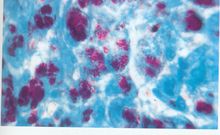

PAS陽性為紅色,細胞核藍色。

陽性反應,胞漿呈紅色, 陰性反應,胞漿呈無色;

在正常血片中RBC不染色;

PLT染成深紅色;

中性粒細胞胞漿染成紅色或深紅色,有些細胞有陽性顆粒;

單核細胞的胞漿染成淡紅色,可含有細小或粗大陽性顆粒;

少數淋巴細胞的胞漿內含有少許小的淡紅色或紅色顆粒;

正常骨髓的 幼稚細胞和有核 RBC都不染色;

巨核細胞的胞漿內呈彌散紅色或深紅色。